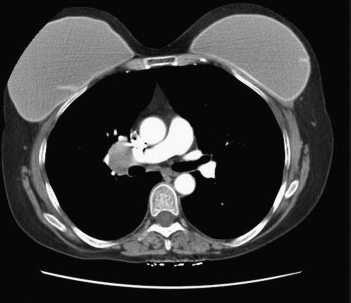

병원가서 CT찍음 다 이렇게나온다 의료계종사자임 사진은 구글펌

이미지확대보기